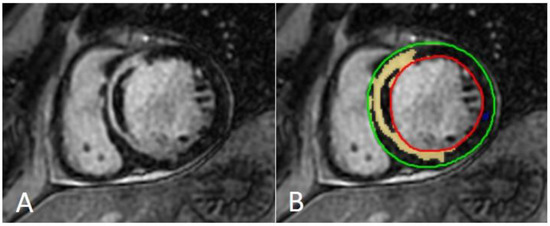

Figure 7.

Image segmentation platform. Functional and volume analysis to obtain ejection fraction, volumes, stroke volume, cardiac index, and left ventricle mass in end diastolic phase. Green: epicardial contour; red: endocardial contour; yellow: right ventricle. EDV—end diastolic volume; ESV—end systolic volume; SV—stroke volume; EF—ejection fraction; CO—cardiac output; CI—cardiac index.